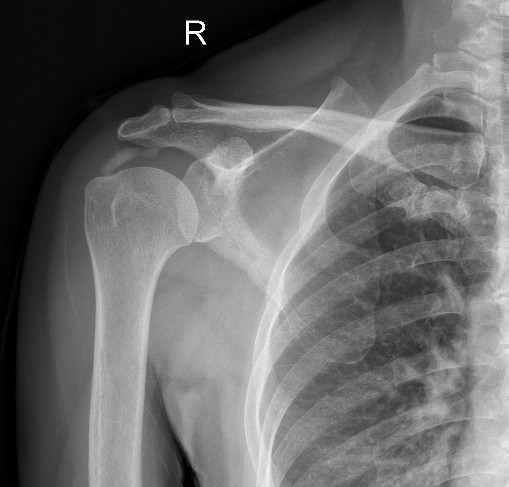

术前X光片显示肩袖区钙化灶